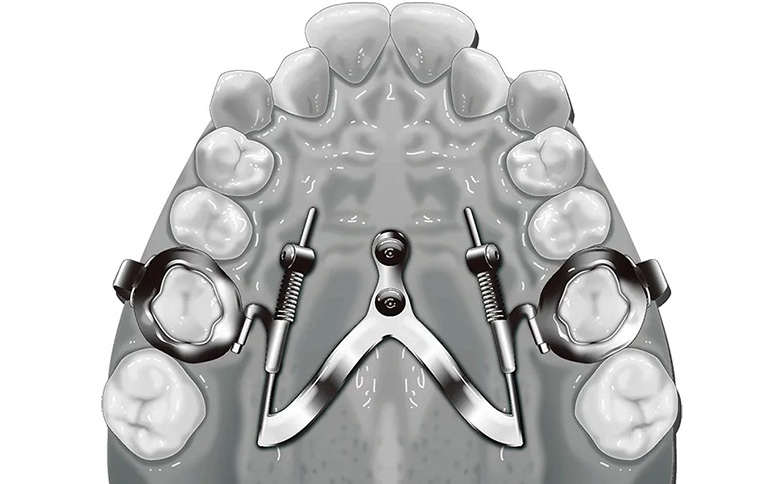

シューライダー装置

(SHU-lider®)

シューライダー装置(SHU-lider®)は、歯を傾けるのではなく、歯根ごと平行に移動させる「歯体移動」が可能な矯正装置です。特に上顎犬歯を十分に後方へ歯体移動できる点が特長で、前歯や歯槽骨、歯肉も含めて口元全体を後方へ下げることが可能です。さらに症例によっては大臼歯の遠心移動を行うことでスペースを確保し、小臼歯を抜歯せずに治療できる可能性が広がります。